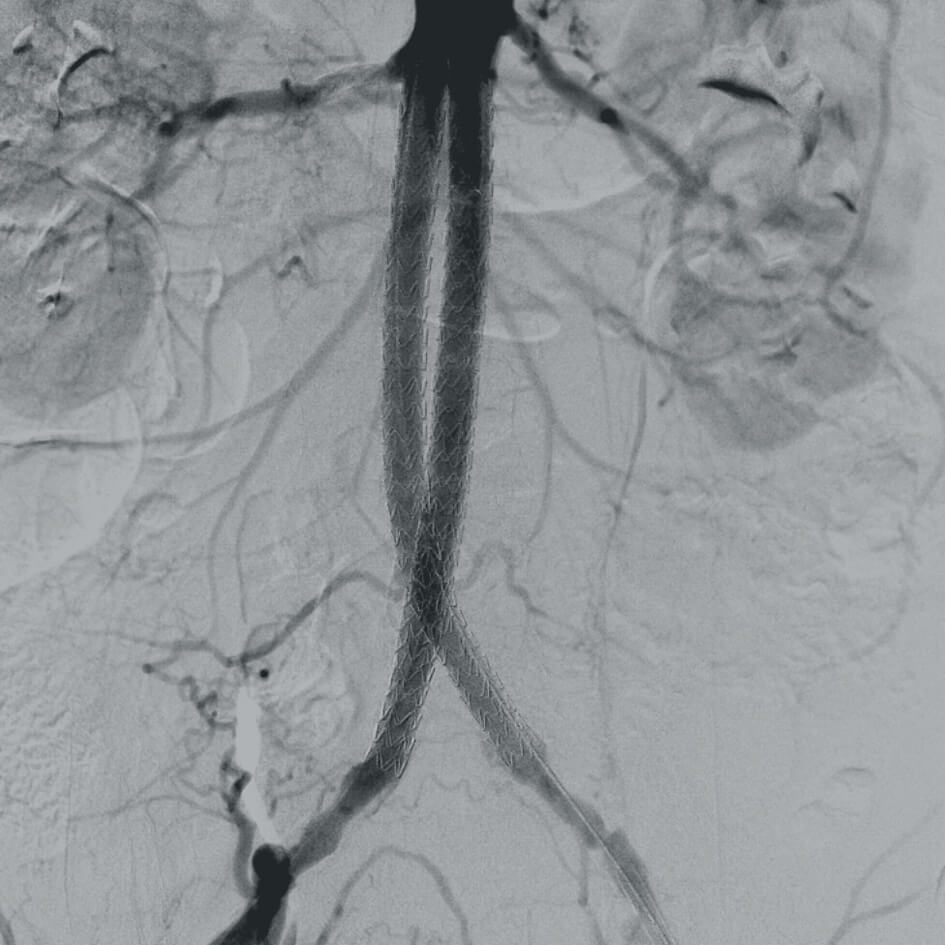

Полное отсутствие искажений снимков в сочетании с высоким динамическим диапазоном широко востребованы как при сложных операциях в нейрохирургии, сосудистой хирургии, инвазивной радиологии, так и в гибридных областях применения, а также в ортопедии, травматологии. В сосудистой хирургии особенно важны высокий динамический диапазон и пространственное разрешение, обеспечивающие детальную визуализацию даже мельчайших сосудов. Специализированное программное обеспечение SmartVascular позволяет проводить настройку системы для васкулярных операций и сосудистой хирургии.

- программный пакет для сосудистой хирургии,

- субтракционная ангиография с применением СО2.